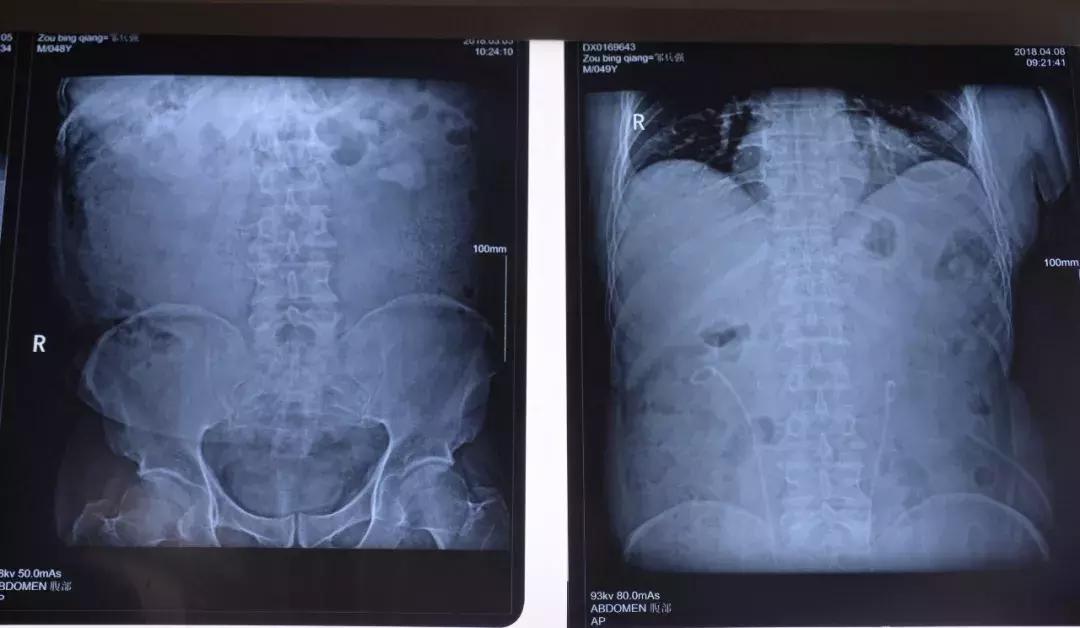

术前X光片 术后X光片

术后复查腹部平片无残余结石。目前,邹先生恢复良好,并康复出院。他对医院外科的高超技术表示高度赞扬,感谢医院医护人员为他解除了病痛折磨。